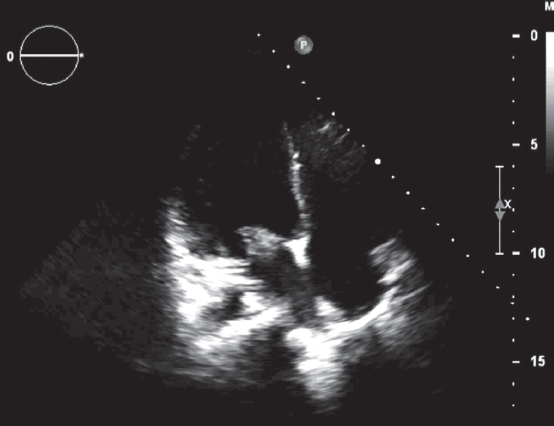

The optimal time for surgery on the heart valves in patients with active infectious endocarditis (IE) is still controversial. It is a well known fact that cerebral, coronary or renal thromboembolism is the most common cause of death in patients with left-sided IE. Thromboembolism can develop before the appearance of clinical manifestations of the destruction of the valvular apparatus of the heart. Currently, early surgical intervention is considered as the most effective method of treatment of many forms of active left-sided IE. Early surgery involves performing surgical correction until the completion of a full antibiotics course. We present the clinical case of early surgical correction of the patient (A., 16 years) with mitral valve infectious endocarditis. The disease was acute, with recurrent embolisms to the right kidney with infarction and to the left clavicle with osteomyelitis. Surgical intervention was performed as a matter of urgency; surgical access – right-sided anterolateral thoracotomy. The girl was operated on the 4th day of the hospitalization to our hospital. However, time of treatment was lost at the prehospital stage and rapid mitral valve destruction did not allow to repair the valve. Therefore, the mitral valve replacement was performed. The postoperative period was favorable. On the 3rd day after the operation, the girl was transferred to the cardiology department. On control ECHO after 3 years: myocardial contractile function is good, EF 65%, the function of the MV prosthesis is not impaired.